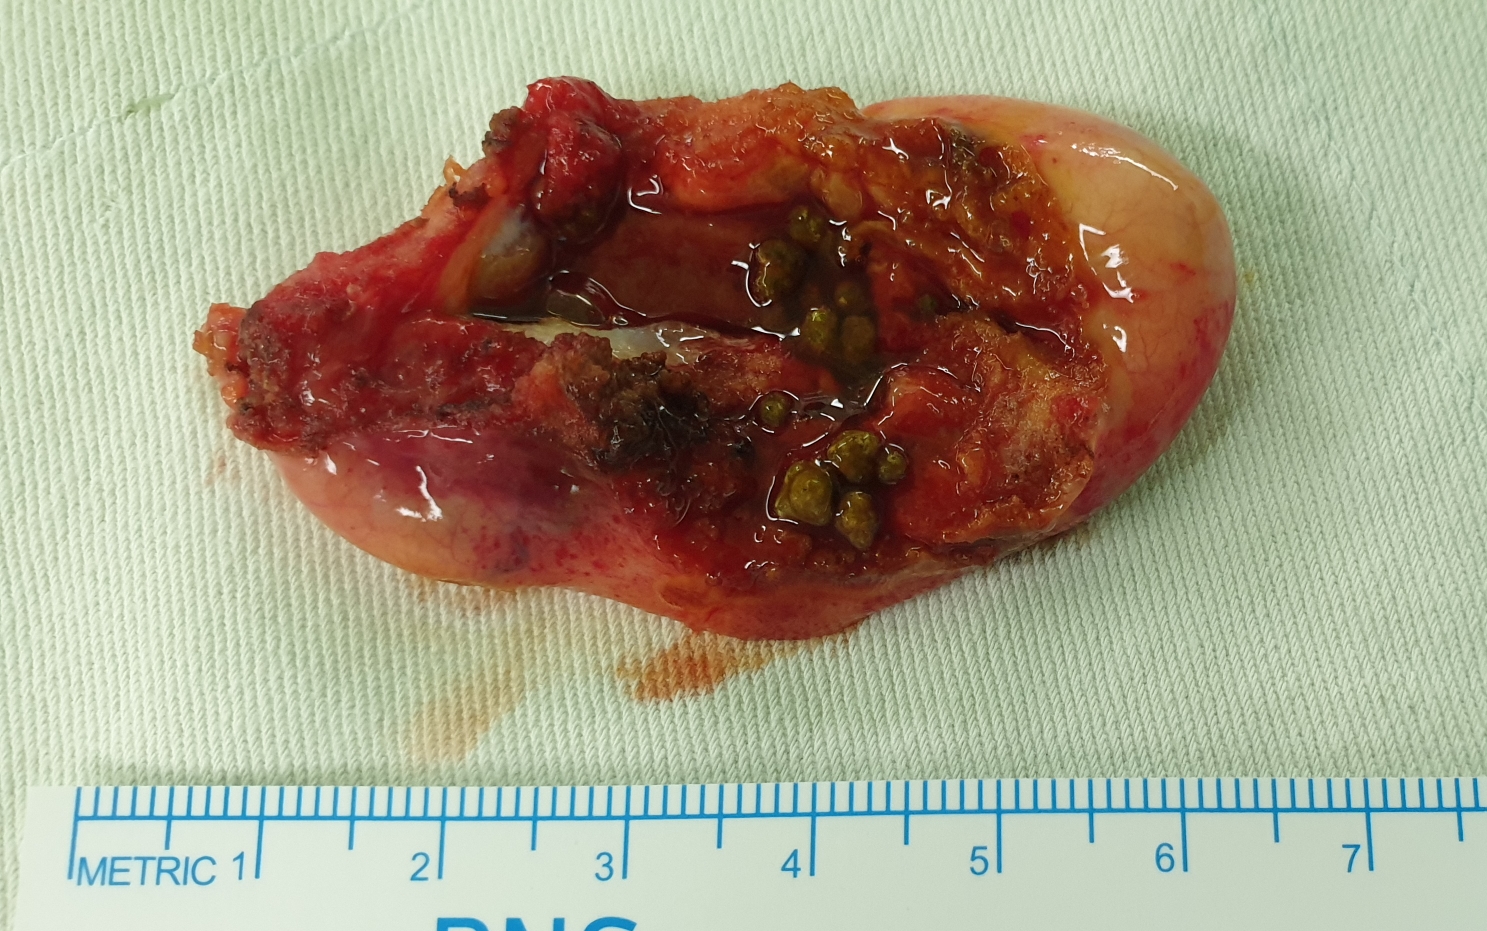

4번째 담낭절제술 시행한 분입니다.

특별한 합병증없이 잘 끝났습니다.